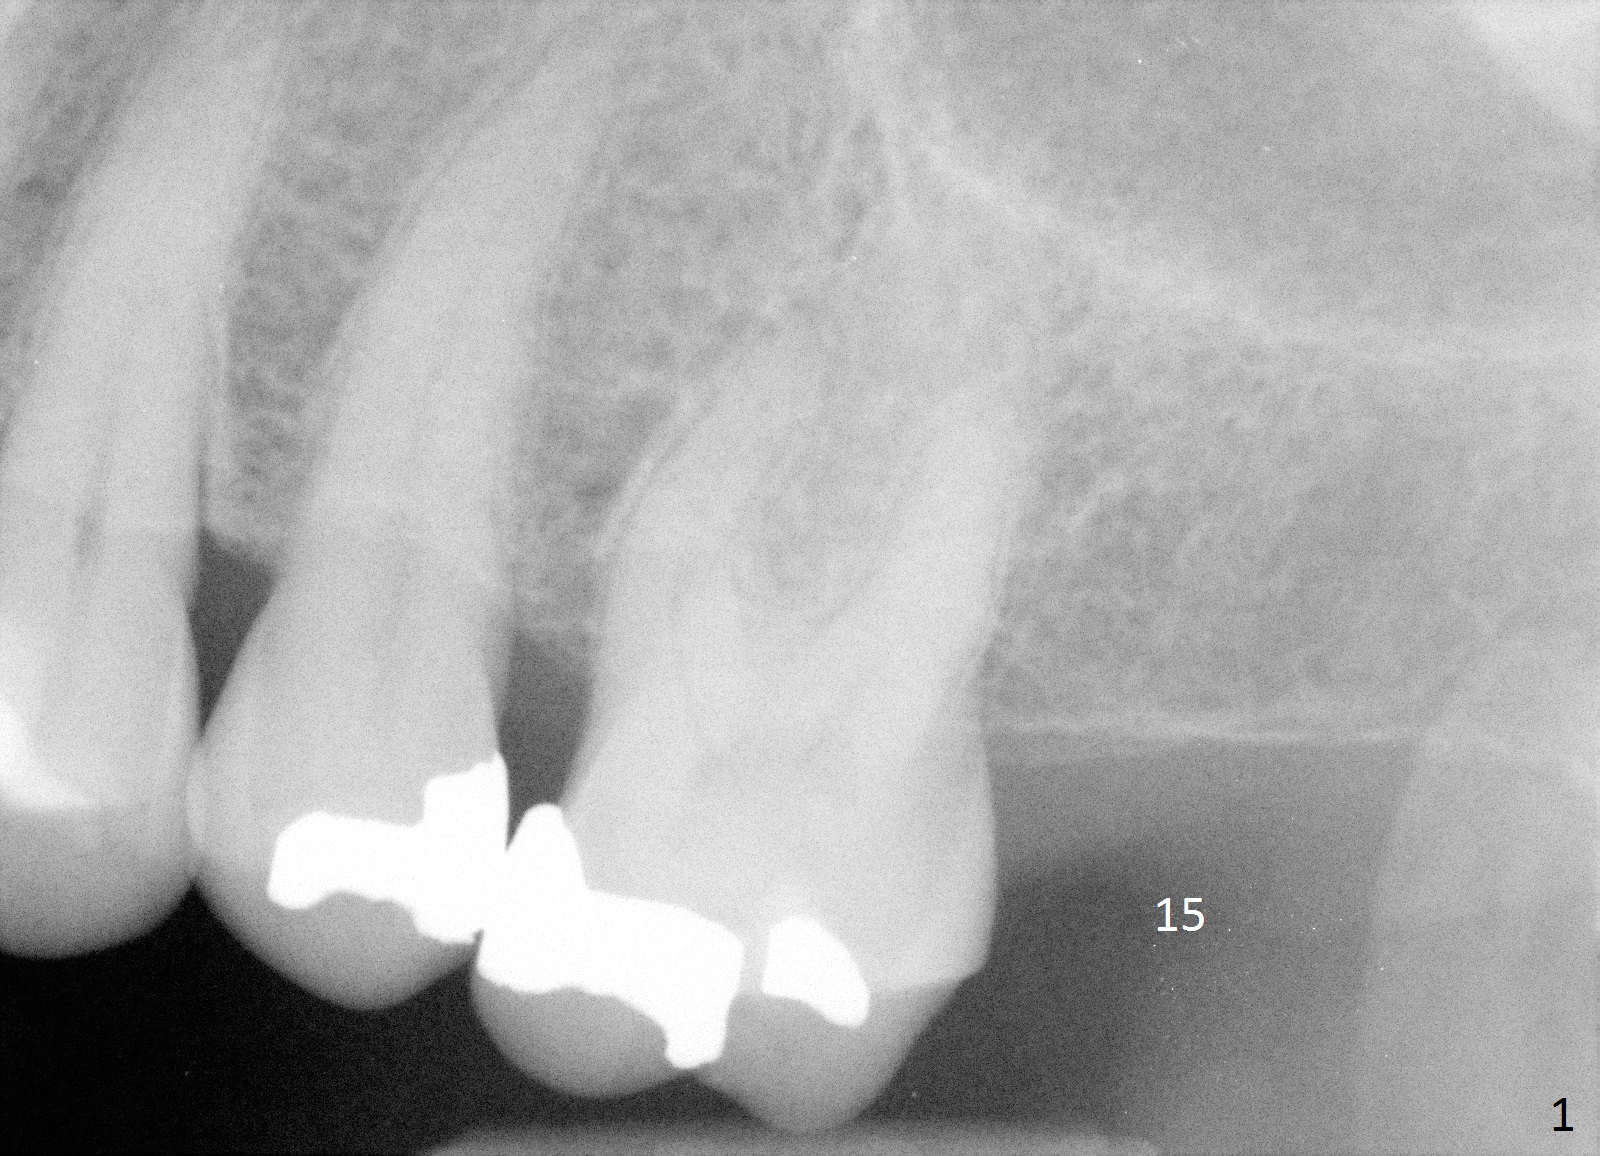

A 65-year-old woman will return to have an implant placed at the site of #15 a few years after that at #19 (Fig.1). Clinically there is limited vertical clearance and the ridge is narrow. These 2 problems will be handled with placement of the implant deep and use of bone expanders, respectively. To protect the sinus membrane, the initial osteotomy depth is going to be 10 mm (9-1+2 mm, Fig.2) with an increase of 1 mm in depth with each of the bone expanders. Take PA with the initial drill. Prepare IBS implant and the one used last time for the patient, including healing and restorative abutments.